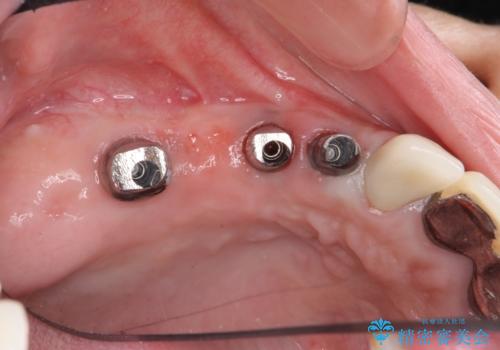

既に埋入されているインプラントは位置が悪いのでそのまま骨内に留置することとし、新たに咬合機能を回復すべく3本のインプラントを埋入すると同時に吸収した骨幅を増やし、安定してインプラントで噛める環境整備を目指します。

インプラントが長持ちするために、インプラント周囲の十分な骨量・角化歯肉の存在・安定した咬合を一つづつ整備する治療を行いました。